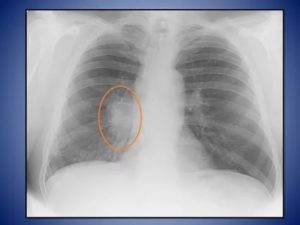

Синдром круглой тени констатирую тогда, когда пятно на легких имеет круглую или овальную форму на двух выполненных перпендикулярно друг другу снимках, то есть спереди и сбоку. Для расшифровки результатов рентгенографии при обнаружении круглой тени опираются на 4 признака:

- форма затемнения;

- локализация затемнения относительно близлежащих органов;

- четкость и толщина ее контуров;

- структура внутреннего поля тени.

Поскольку тень, отраженная на снимке, в пределах легочного поля, может в действительности находиться за его пределами, оценка формы затемнения может существенно облегчить диагностику.

Так, округлая форма характерна для внутрилегочных образований (опухоль, киста, инфильтрат, наполненный воспалительным содержимым).

Овальная тень в большинстве случаев является результатом сдавливания круглого образования, стенками легкого.

Высокую информативность имеет, и структура внутреннего поля тени.

Если при анализе результатов, очевидна неоднородность тени, например, более светлые очаги, то с высокой степенью вероятности, можно диагностировать распад некрозированной ткани (при распадающемся раке или распаде туберкулезного инфильтрата) или формирование полости. Более темные участки, могут говорить о частичной кальцинации туберкуломы.

Четкий и плотный контур, свидетельствует о наличии фиброзной капсулы, характерной для эхинококковой кисты. К синдрому круглой тени относят только те тени, которые имеют в диаметре более 1 см, тени меньшего диаметра считаются очагами.